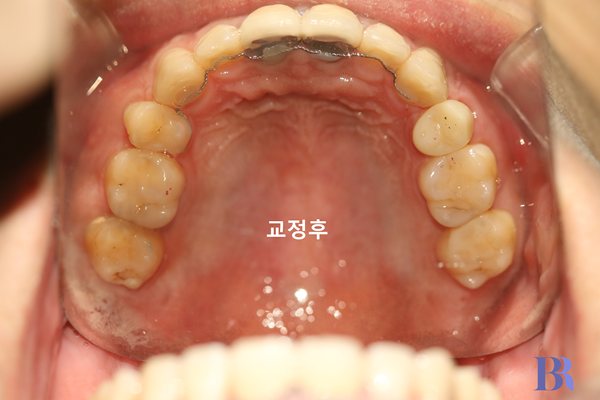

교정 후 입안 윗니 모습

상악 앞니 각도가

치아를 발치한 공간을

폐쇄시키는 동안

쓰러지지 않았습니다.

비교적 건강해 보이네요.